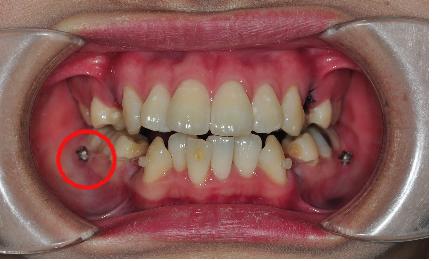

이번 치과방문은 상악에 치아교정 장치를 부착하러 갔습니다.

상악에 좌우 4번 치아를 각각 발치를 했는데요.

그리고 나서 하악 송곳니에 동그란 가짜치아(?) 를 만들어 주셧어요

이것과 스크류를 고무줄로 연결해서 송곳니를 당긴답니다!~

저는 하악에 좌우 1번 2번 치아 사이에 스크류를 심었어요.